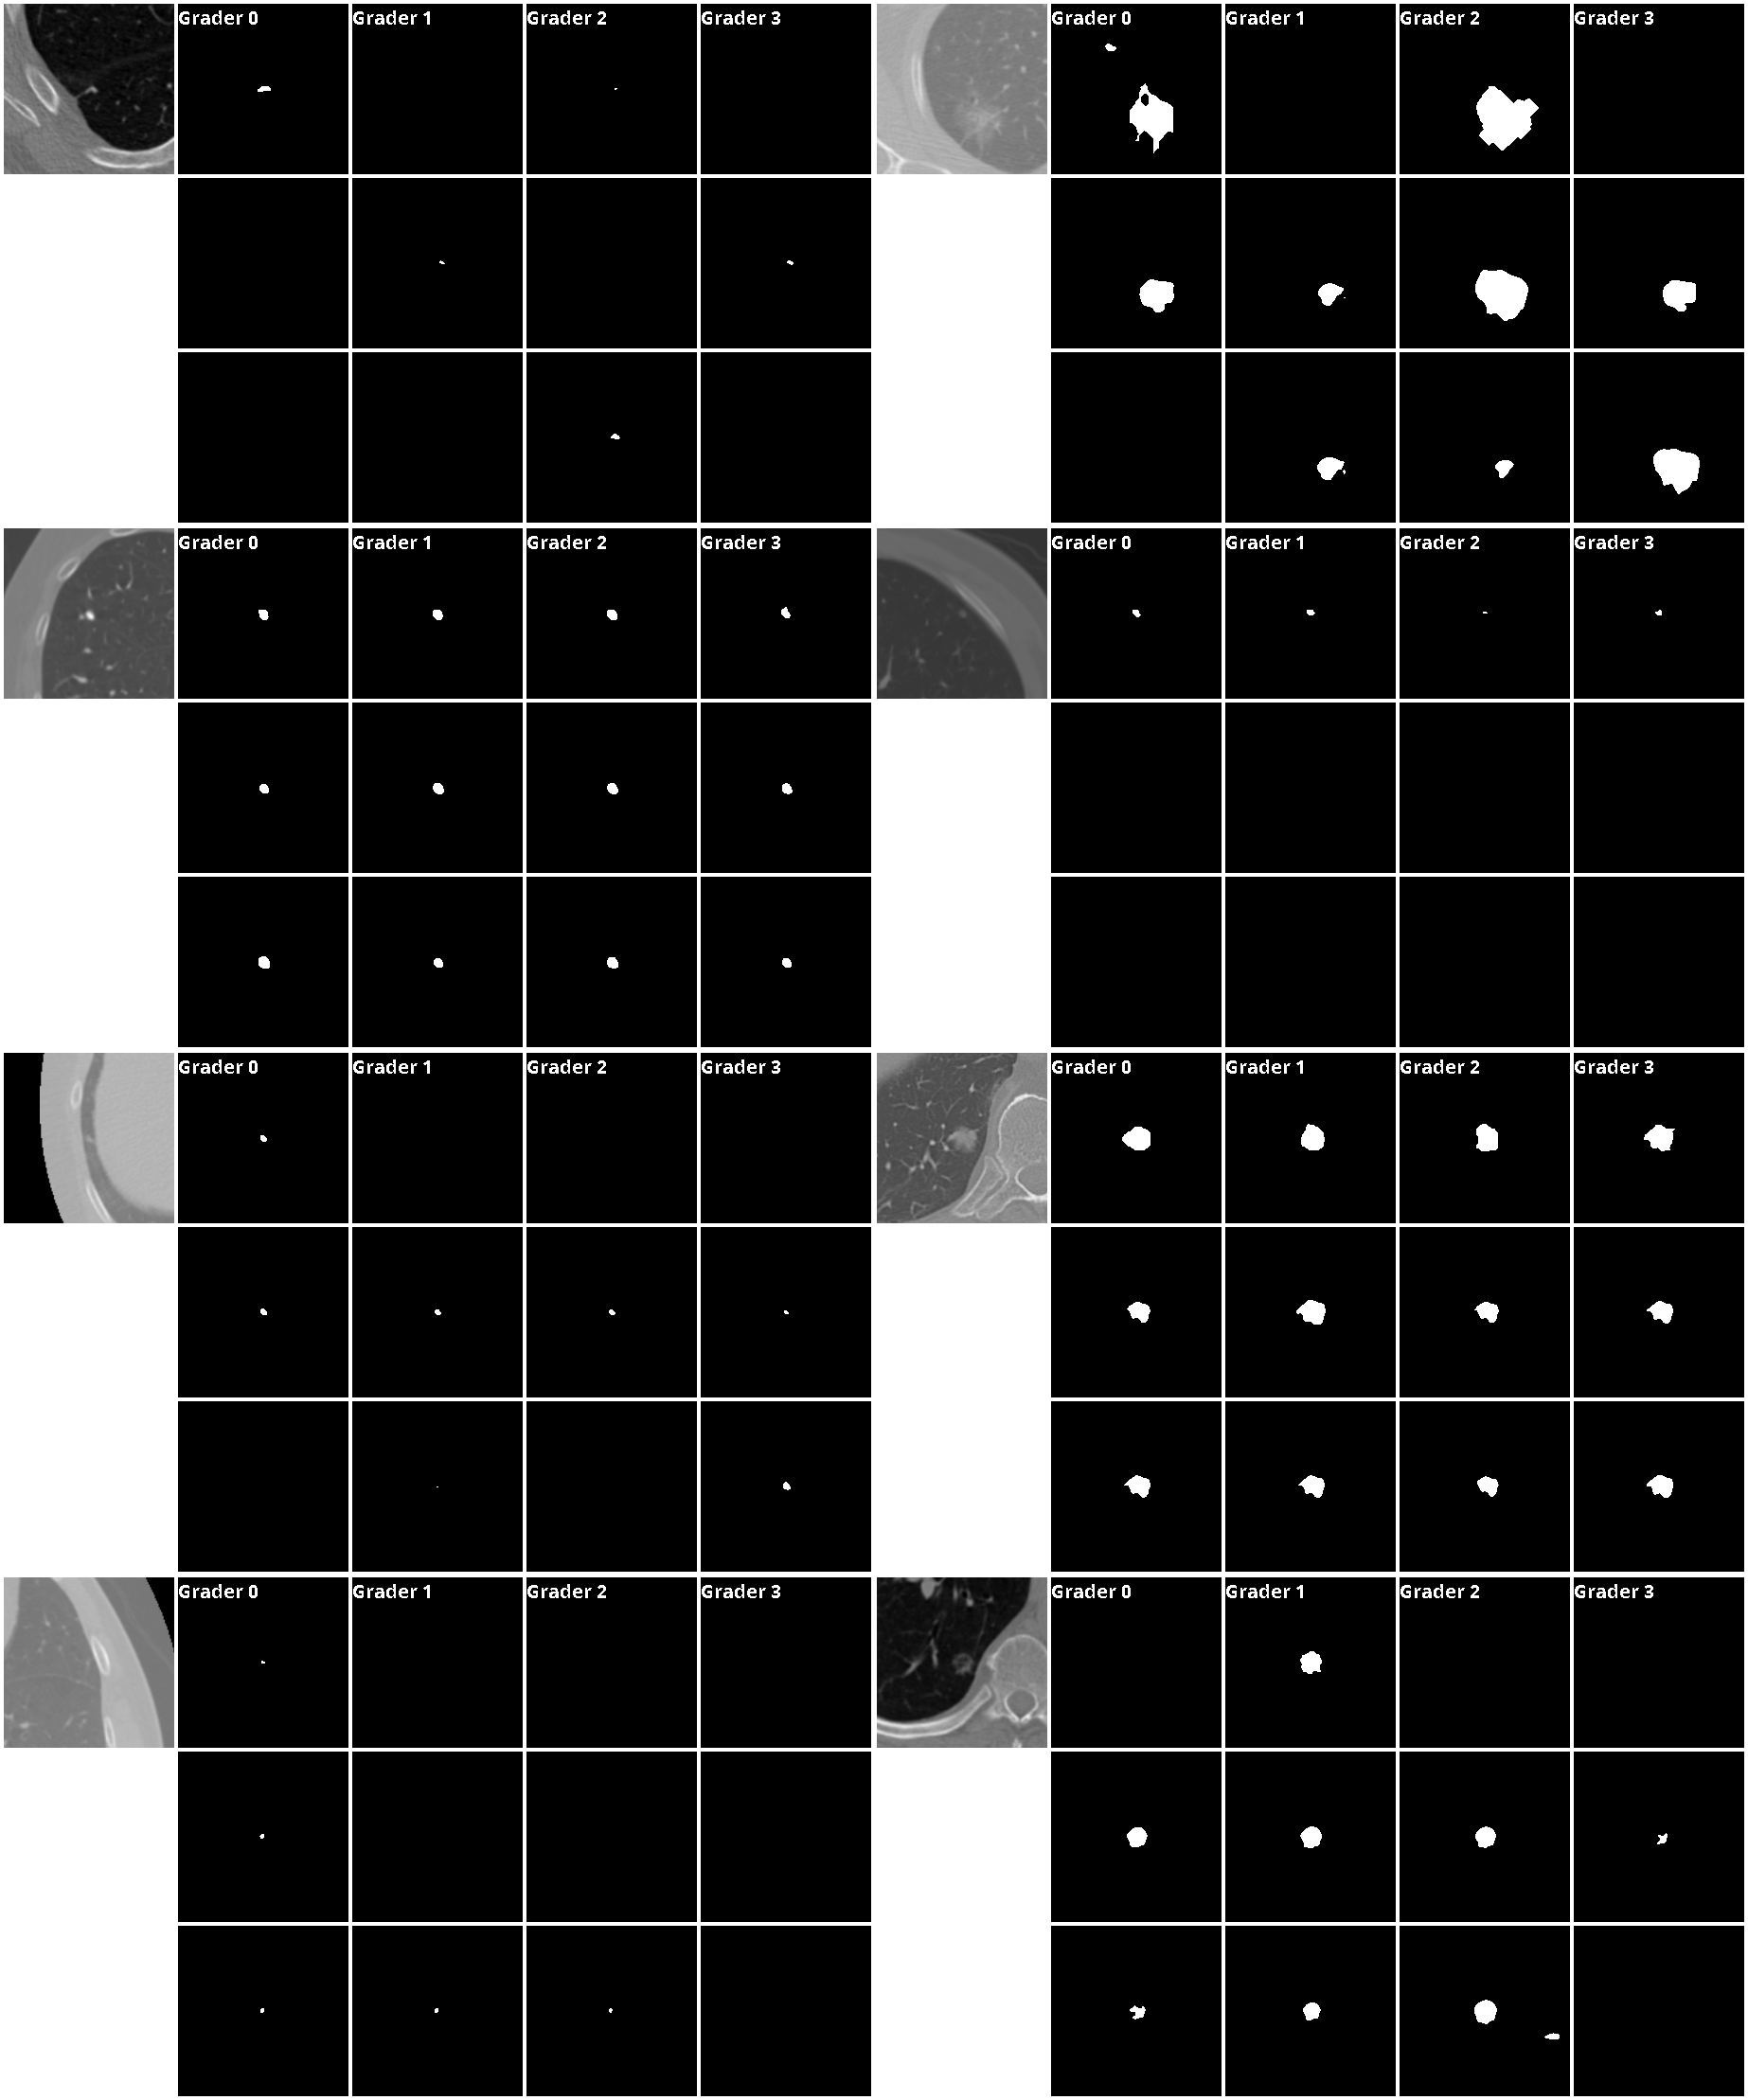

Some additional results from our model and Probabilistic U-Net are shown in Fig.8,9 and Fig.10, 11, respectively.

Figure 8: Results from our model on the LIDC-IDRI segmentation task. Top-8 results with the predicted uncertainties are shown.

Refer to caption

Figure 9: Results from our model on the LIDC-IDRI segmentation task. Top-8 results with the predicted uncertainties are shown.

Figure 10: Results from Probabilistic U-Net on the LIDC-IDRI segmentation task. 8 random samples are shown.

Figure 11: Results from Probabilistic U-Net on the LIDC-IDRI segmentation task. 8 random samples are shown.